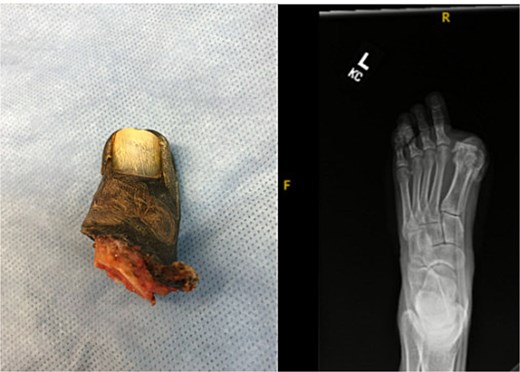

On postoperative day 1, the great toe became blue and painful. Vascular consultation was obtained. Angiography demonstrated impaired distal perfusion without a correctable lesion. Despite wound care, debridement, hyperbaric oxygen therapy, and oral cephalexin, the toe progressed to dry gangrene involving the entire hallux (Fig. 2). On examination, gangrene extended to the MTP joint with surrounding hyperemia but no erythema. The hallux lacked capillary refill and sensation, yet dorsalis pedis and posterior tibial pulses were 2+ (normal amplitude). Sensation and motor strength in the lesser toes were intact.

At 8 weeks, she underwent left hallux amputation at the MTP joint with removal of both screws, resection of nonviable tissue, and application of negative pressure wound therapy (NPWT) (Fig. 3). Intraoperative cultures demonstrated polymicrobial growth, including Pseudomonas aeruginosa and Staphylococcus aureus. She was treated with oral trimethoprim–sulfamethoxazole based on susceptibilities and infectious disease recommendations, with continued NPWT. The wound healed uneventfully, and she returned to full activity. Following wound healing, she was fitted with a custom great toe prosthetic device (Fig. 4). At 1 year, she reported no pain and had resumed gym workouts without limitation. Clinical examination showed good prosthetic function (Fig. 5), and radiographs demonstrated satisfactory healing (Fig. 6).

Gross specimen of amputated hallux (left) and postoperative radiograph following metatarsophalangeal joint amputation and screw removal.